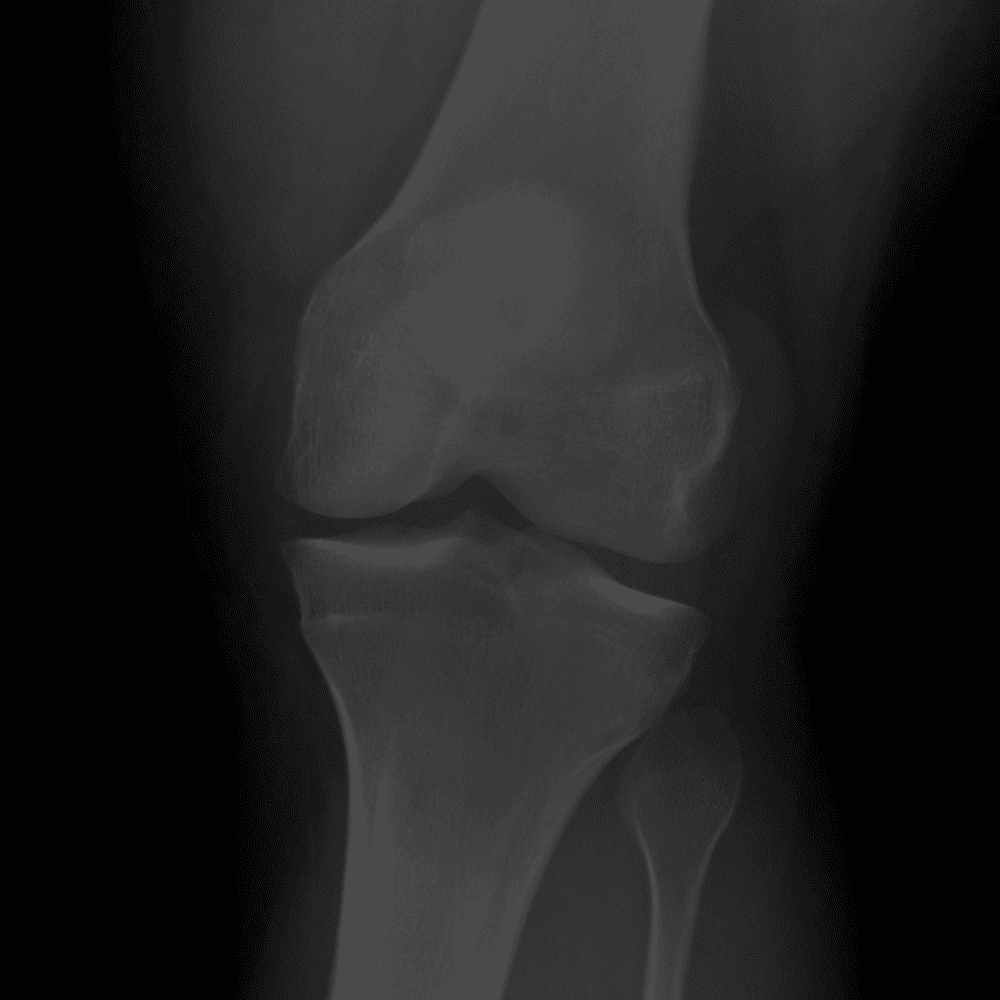

Simula o plantão incluindo casos sutis ou difíceis e alguns normais.